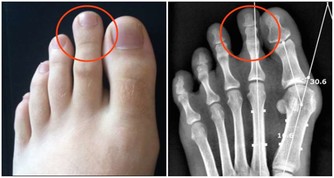

肝硬化等疾病,會造成靜脈的血液回流不通暢,也會讓肚臍周圍的血管曲張,而造成特殊的「海蛇頭」樣變化。